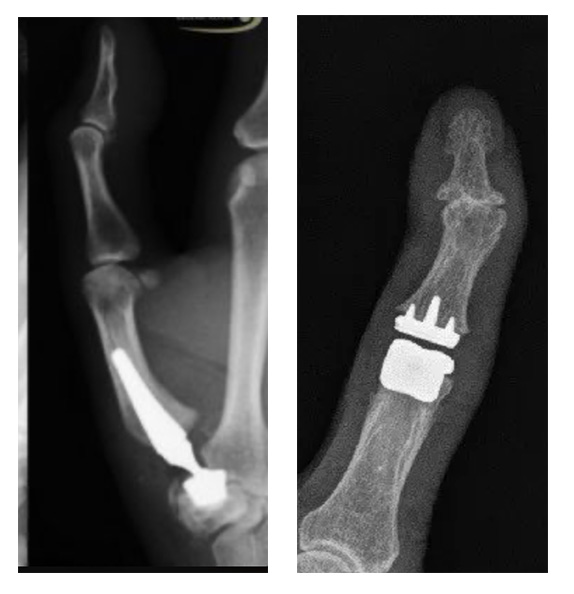

Joint Replacement

Constantly painful joints greatly impair hand function, and chronic pain takes a toll on the mind… In cases of osteoarthritis, some joints an be replaced. These endoprostheses can preserve mobility and, in many cases, restore pain-free use of the finger joints. These modern surgical procedures are a good alternative to joint fusion (arthrodesis) or other surgical therapies.